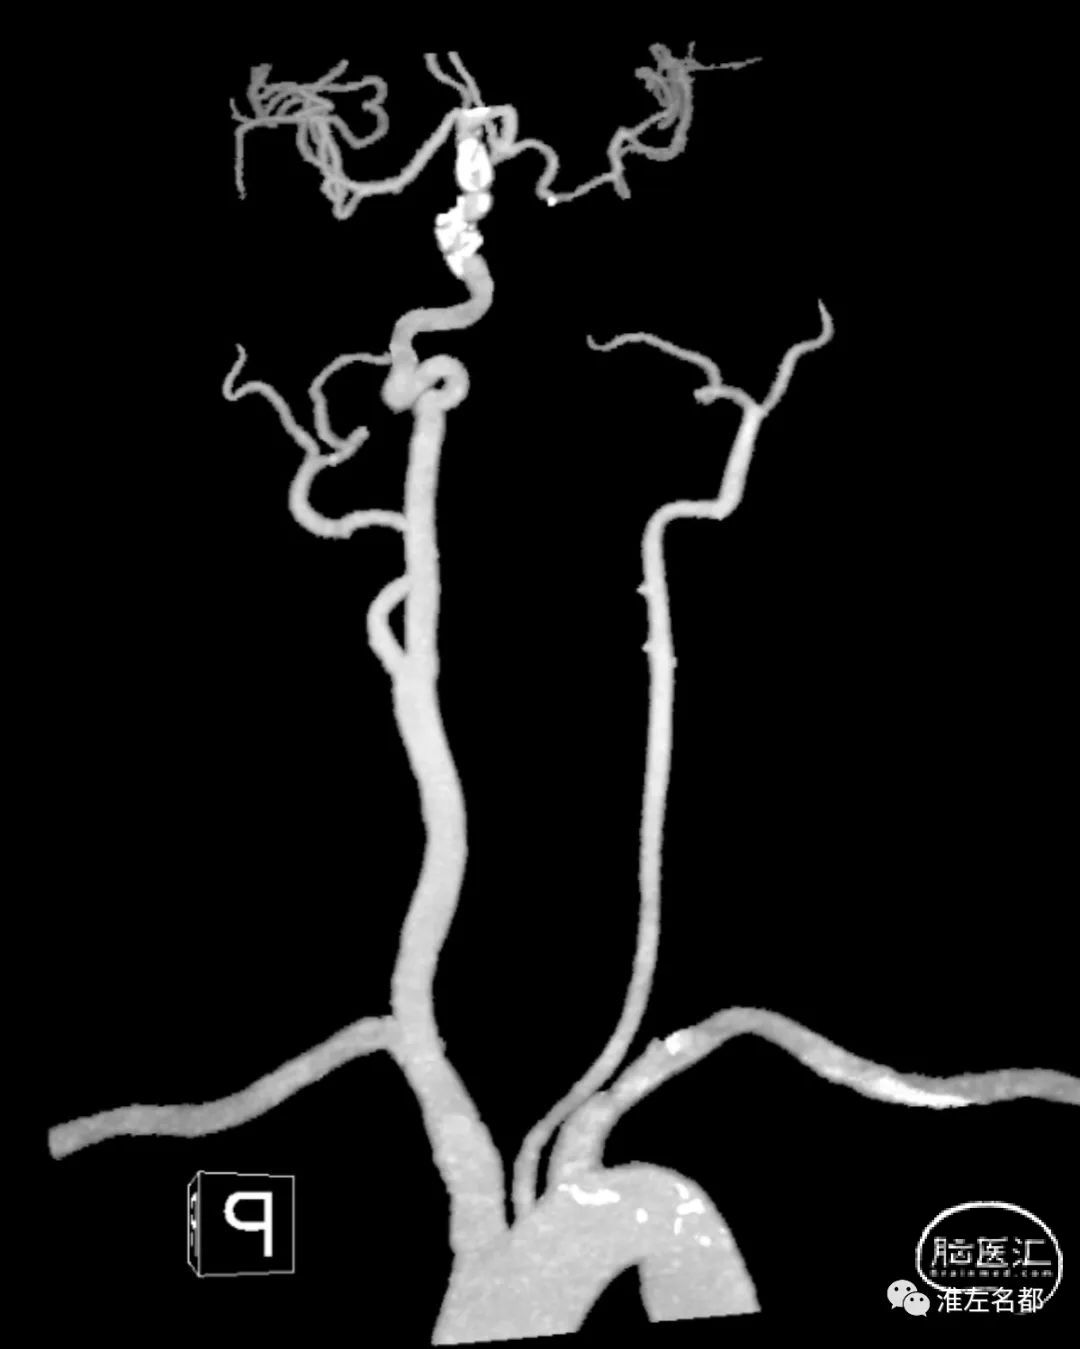

颈部CTA:左侧颈总动脉明显细小,左侧颈内动脉未见显影。

颅脑CTA:前交通动脉局部小动脉瘤。